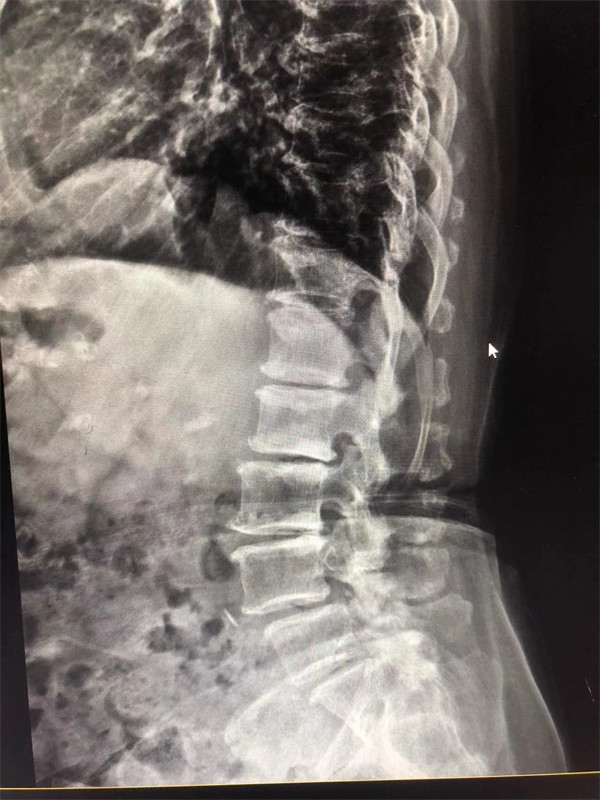

手術(shù)前↓

戈主任仔細(xì)詢問阿婆病情癥狀,綜合查體及MRI片情況,認(rèn)為阿婆有明顯的腰椎滑脫,腰椎管狹窄,這是引發(fā)阿婆病痛的主要因素。

阿婆曾在院外多家醫(yī)院就醫(yī),被診斷為腰4椎體滑脫癥、腰椎管狹窄癥、腰椎間盤突出癥,外院予以止痛、理療、針灸等各種保守方式治療,病情未見明顯改善。